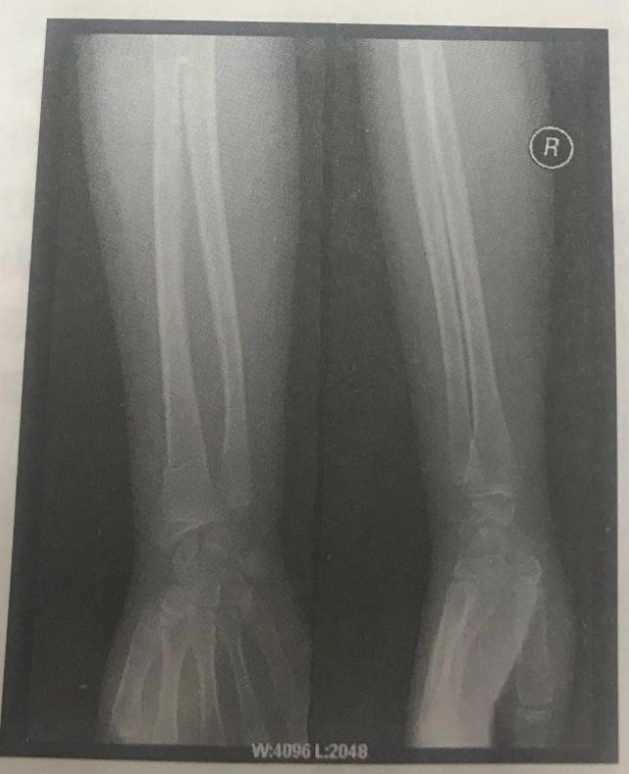

根據(jù)下面X線片判斷臨床意義。(5分)

右撓骨遠(yuǎn)端青枝骨折。